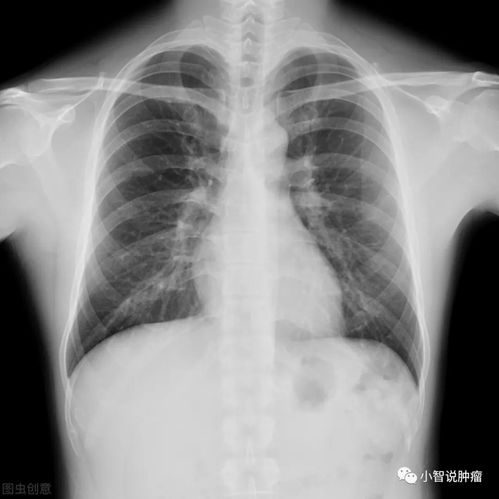

第二章:视野的局限——胸片在肺癌筛查中的“盲区”

胸部X光片是一种利用X射线穿透胸部组织形成二维重叠影像的检查方法。它经济、快捷、辐射剂量较低,长期以来是肺部疾病筛查的入门手段^。正是其工作原理和成像特点,决定了它在捕捉早期肺癌信号时存在多重“盲区”^。

1. 分辨率与密度限制:胸片对组织密度的分辨率有限。早期肺癌,尤其是表现为磨玻璃结节(一种淡薄的、云雾状的阴影)的腺癌,其密度很低,在胸片上极易与正常肺组织或血管影混淆,难以辨识^。研究表明,胸片对直径小于1厘米,特别是小于5毫米的结节,检出率极低^。

2. 结构重叠与遮挡:胸片是前后组织结构的二维叠加影像。心脏、纵隔、大血管、膈肌以及肋骨会与肺部影像重叠,形成天然的“视觉屏障”。生长在这些区域后面的病灶,如位于肺尖、脊柱旁、心影后或膈肌后方的肿瘤,很容易被完全遮挡而无法显示^。这正是“拍胸片无异常,但病灶实际存在”的最常见解剖学原因^。

3. 定性能力不足:即便胸片发现了一个可疑阴影,它也无法准确判断该阴影的性质是良性(如炎症、结核球)还是恶性^。确诊仍需依赖更精密的检查。胸片阴性不能完全排除肺癌,胸片阳性也不等于就是肺癌^。

4. 动态发展的时差:肺癌是一个动态生长的过程。半年前,病灶可能确实非常微小,处于胸片分辨能力的极限之下,或恰好位于重叠遮挡区。在随后的几个月里,肿瘤细胞持续增殖,当体积增大到足以在胸片上显现,或引起阻塞性肺炎、肺不张等继发改变时,才被“看见”^。这个“时间窗口”恰恰是早期干预的黄金时期,却被胸片漏过了。

多项权威研究证实,使用低剂量螺旋CT进行肺癌筛查,对早期肺癌的检出率是传统胸片的4到10倍,能发现更多可治愈的早期病变,从而显著降低肺癌死亡率^。